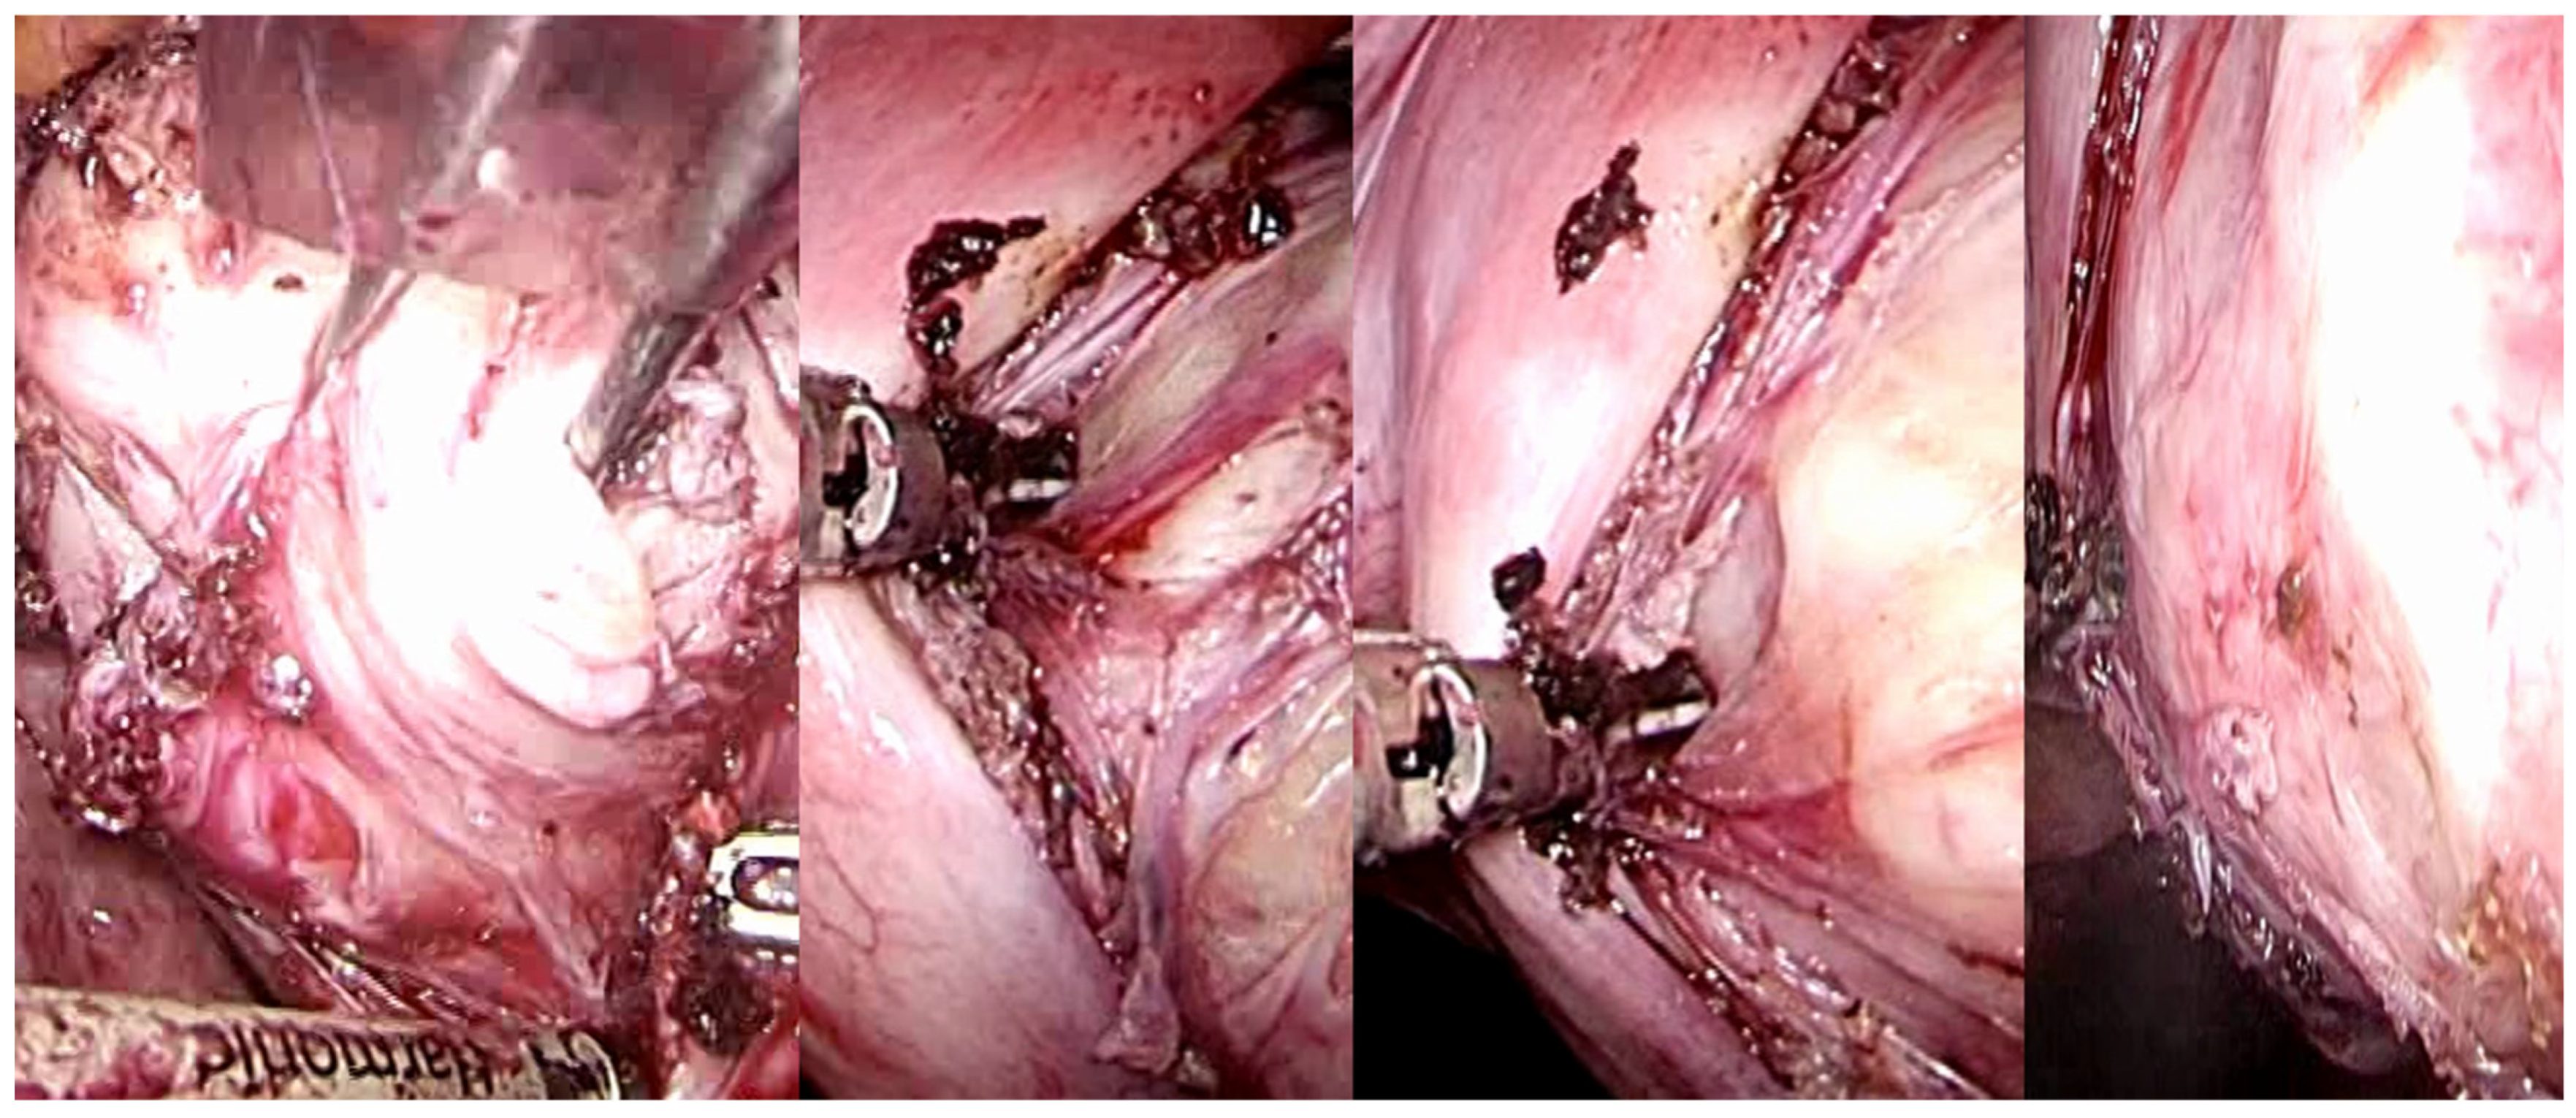

Uterine fibroids, during their growth, facilitate the progressive development of a peripheral surgical-anatomical biological structure known as myoma pseudocapsule [37,38]. This anatomical entity, which remained largely unrecognized for numerous years, has garnered significant interest among gynecologists specializing in fertility surgery in the contemporary century. This biological structure arises from the compression of the surrounding myometrium by the fibroid, creating a separation, albeit minimal, between the fibroid and the healthy myometrium. In succinct terms, the pseudocapsule displaces the intact myometrial muscular fibers, functioning as a delicate fibromuscular barrier, thereby preserving the integrity and contractility of the uterine musculature. Moreover, from an anatomical perspective, the uterine fibroid is structurally linked to its pseudocapsule via connective bridges; however, it is devoid of its own true vascular pedicle and, on occasion, possesses vascular and collagen fiber bridges that anchor the myoma to the myometrium, thus disrupting the surface of the pseudocapsule [37] (Figure 6).

Figure 6.

Laparoscopic image of intracapsular myomectomy. From left, progressive identification of the fibroid (in white, hooked with Collins’s forceps) with the pseudocapsule branches covering it and subsequent incision of the fibrovascular branches of the pseudocapsule to detach and enucleate the fibroid from the pseudocapsule, with minimal blood loss and less myometrial damage.

Thus, the intracapsular myomectomy procedure is predicated upon the principles of muscular physiology while concurrently adhering to anatomical considerations. By selectively coagulating the fibroneurovascular bundles of the network surrounding the fibroid, the proper application of the surgical method to biology invariably reduces blood loss during intracapsular myomectomy. Following the incision of the uterine serous surface, one continues deep until they reach the fibroid pseudocapsule, which coagulates and is cut to hook the fibroid and gently drag it outwards while coagulating and dissecting the pseudocapsule’s fibroid neurovascular bundles (Figure 7).

Figure 7.

Laparoscopic image of intracapsular myomectomy. From left, progressive identification of myoma pseudocapsule branches covering fibroid and their subsequent incision to detach and enucleate the fibroid from the pseudocapsule, with better preservation of the myometrium and neurovascular bundle.

Due to the fibroid being vascularized solely through the pseudocapsule’s veins, there can be very little bleeding before and after surgery. The objective remains the selective coagulation of the fibroneurovascular bundles during myomectomy, which allows for the reduction of bleeding to a minimum.

The proper intracapsular myomectomy approach, which selectively coagulates the pseudocapsule vessels, is undoubtedly responsible for the decreased intraoperative blood loss rather than the use of vasopressin or uterine artery occlusion [89].